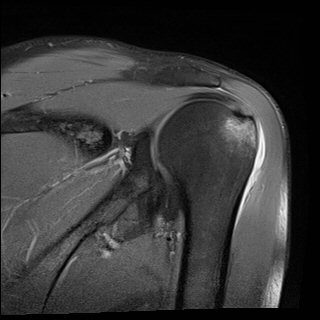

ÀÚ±â°ø¸í°Ë»ç

»ó¿Ï°ñµÎ ´ë°áÀý °ß¿­°ñÀý

±×·¯³ª º» Áõ·Ê¿¡¼­¿Í °°ÀÌ »ó¿Ï°ñµÎÀÇ ¹Ì¼¼°ñÀýÀº ¹æ»ç¼±°Ë»ç¿¡¼­ È®ÀÎÀÌ µÇÁö ¾ÊÀ¸¹Ç·Î

¹æ»ç¼±°Ë»ç¿¡¼­ ÀÌ»ó ¼Ò°ßÀÌ ¾øÀ¸¸é¼­ ½ÉÇÑ ÅëÁõ°ú ±Ù¾àÁõÀ» º¸ÀÌ´Â °æ¿ì´Â ¹Ýµå½Ã ÄÄÇ»ÅÍÃÔ¿µÀ̳ª

ÀÚ±â°ø¸í°Ë»ç¸¦ ½ÃÇàÇÏ¿© °ñÀý ¿©ºÎ¸¦ È®ÀÎÇØ¾ßÇÑ´Ù.

±×·¯³ª ÃÊÀ½ÆÄ°Ë»ç¸¦ ½ÃÇàÇÏ¸é °ñÀý ¿©ºÎ »Ó ¾Æ´Ï¶ó ±Ø»ó°ÇÆÄ¿­µµ È®ÀÎÇÒ ¼ö ÀÖÀ¸¹Ç·Î

¸Å¿ì À¯¿ëÇÑ °Ë»çÀÌ´Ù. ¹°·Ð ÃÊÀ½ÆÄ°Ë»ç·Î °ñÀý¿©ºÎ¸¦ Á¤È®È÷ °¨º°Çϱâ À§Çؼ­´Â ¸¹Àº °æÇè°ú

ÃÊÀ½ÆÄ°Ë»ç ¼Ò°ßÀ» ÄÄÇ»ÅÍÃÔ¿µÀ̳ª ÀÚ±â°ø¸í°Ë»ç ¼Ò°ß°ú ºñ±³ÇÏ´Â ³ë·ÂÀÌ ÇÊ¿äÇÏ´Ù.